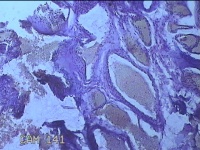

面部肿物

性别

男

年龄

30岁

临床诊断

皮赘;皮肤感染;脚癣

一般病史

面部起疹3月,不痒。

标本名称

大体所见

灰白暗红色肿物0.8x0.5x0.2cm一个,表面糜烂。